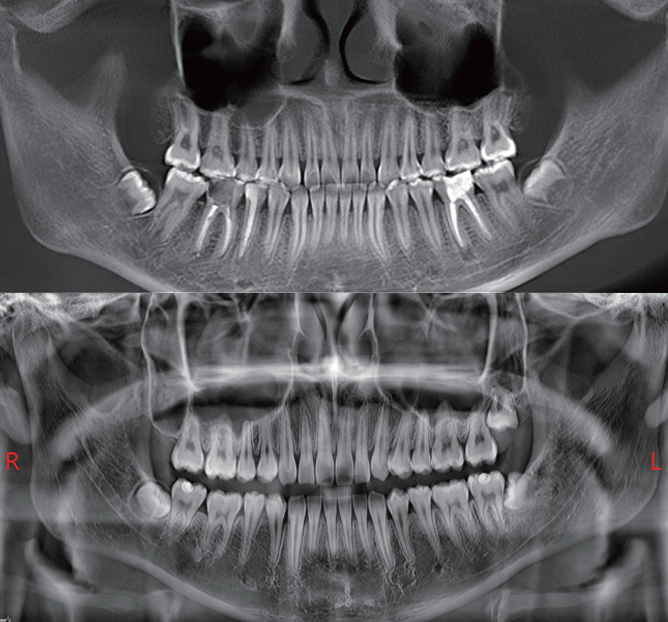

Furthermore, Panoramic Images are Reconstructed from 3D Dental CBCT data for clearer visualization

Furthermore, AI+PAN Dental CBCT Imaging enhances precision.

- The system rebuilds panoramic views directly from CBCT data using AI.

- Panoramic auto-focus and multi-layer technology select the best curve automatically.

- Therefore, the final image is cleaner and easier to read.